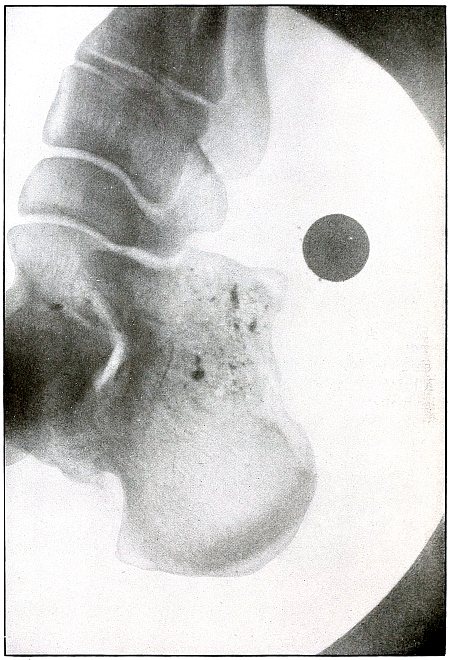

Rifle—Plate 46.

Gunshot Wound of the Pelvis, with Lodgment of the Missile in the Abdomen.

The course of the bullet was from behind forward, striking the crest of the ilium, on which it was deflected, and spattering off some lead fragments. The slight penetration indicates a velocity of extremely long range and a striking energy lessened by ricochet.

The irregular outline of the shadow of the projectile shows its deformity, and the blurred outline indicates intra-abdominal movement with respiration.

While the missile, as revealed by its shadow, is not a shrapnel ball, the distribution of lead particles is more suggestive of a shrapnel than of a rifle projectile, and the ballistic conditions are more characteristic of the former than of the latter.

There was no abdominal reaction; the invasion of the abdomen was revealed by the radiograph.

The treatment in such cases is noninterference unless subsequent developments furnish definite indications. [Pg 104]